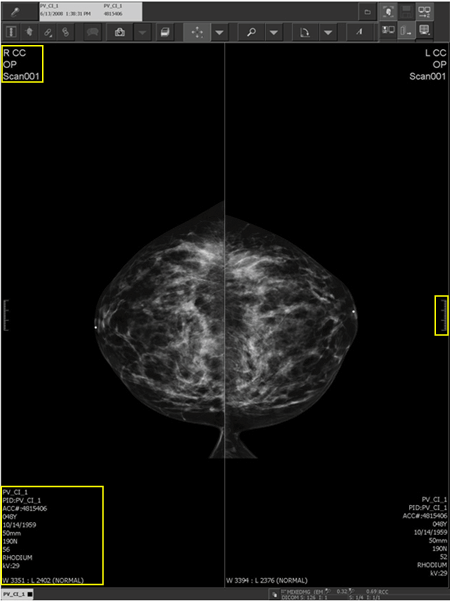

A 3 cm scale (highlighted by the yellow rectangle on the right side of the image) on the non-chest wall side of all breast images is visible to indicate the physical size of the displayed image. It helps to provide a visual clue to the general size of the features in the image. You can show or hide the ruler, along with the demographics.

When breast imaging demographics are configured on the left-hand side of the Demographic Layout Manager in the IMPAX Administration Tools (highlighted by the two yellow rectangles on the left side of the image), the demographics flip when displayed or printed so they always appear on the non-chest wall side. The laterality and view_position information appear in larger fonts and accurately reflect the ACR defined view, with complete and accurate view modifiers.

Breast imaging demographics example